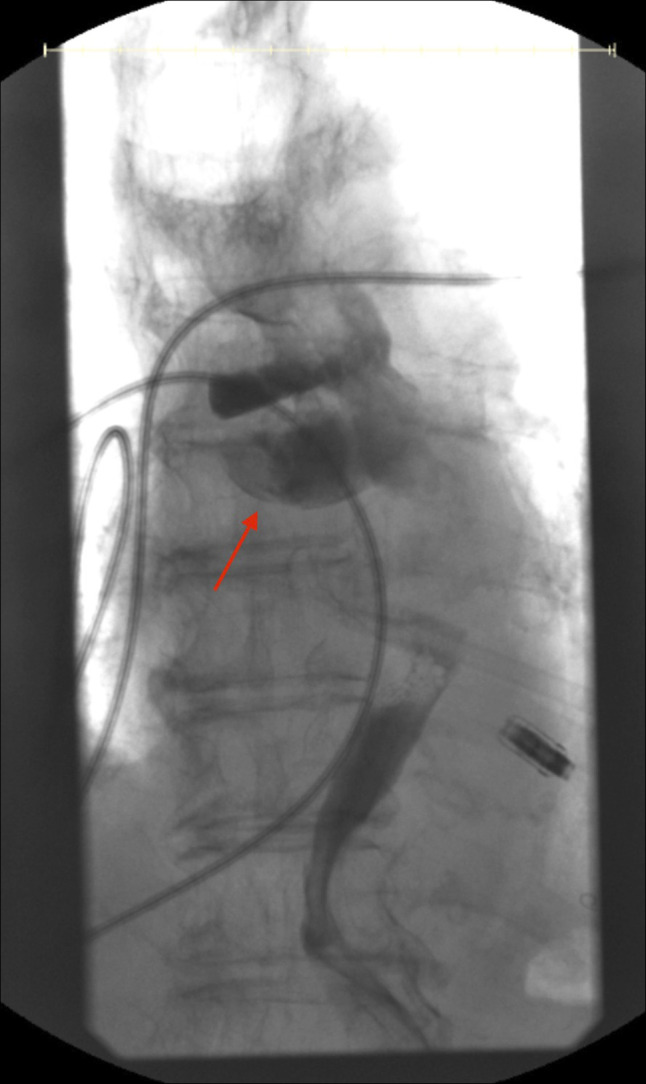

经食管超声心动图通常用于指导结构性心脏干预,但有食管损伤的风险。我们报告一位79岁的女性,她接受了经导管二尖瓣边缘修复术,并发食道血肿。急性胆囊炎并发难治性消化道出血及败血症。尽管采取了积极的措施,她还是没能活下来。我们的病例显示了经食管超声心动图相关并发症的潜在严重性,特别是在有食道憩室和抗凝使用等易感因素的患者中。

Transesophageal echocardiography is commonly used to guide structural cardiac interventions but carries a risk of esophageal injury. We present a 79-year-old woman who underwent a Transcatheter Edge-to-Edge Repair of the mitral valve and developed an esophageal hematoma. Clinical course was complicated by intractable gastrointestinal bleeding and sepsis due to acute cholecystitis. She did not survive despite aggressive measures. Our case demonstrates the potential severity of transesophageal echocardiography-related complications, especially in patients with predisposing factors such as esophageal diverticula and anticoagulation use.